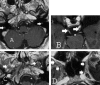

Fig 2.

A–C, Thin-section (1-mm) coronal and axial CT images of the skull base obtained with an edge-enhancing bone algorithm show enlargement (arrows) of the mastoid canals of cranial nerve VII (A), the foramina of ovale (B), and rotundum (C) bilaterally.